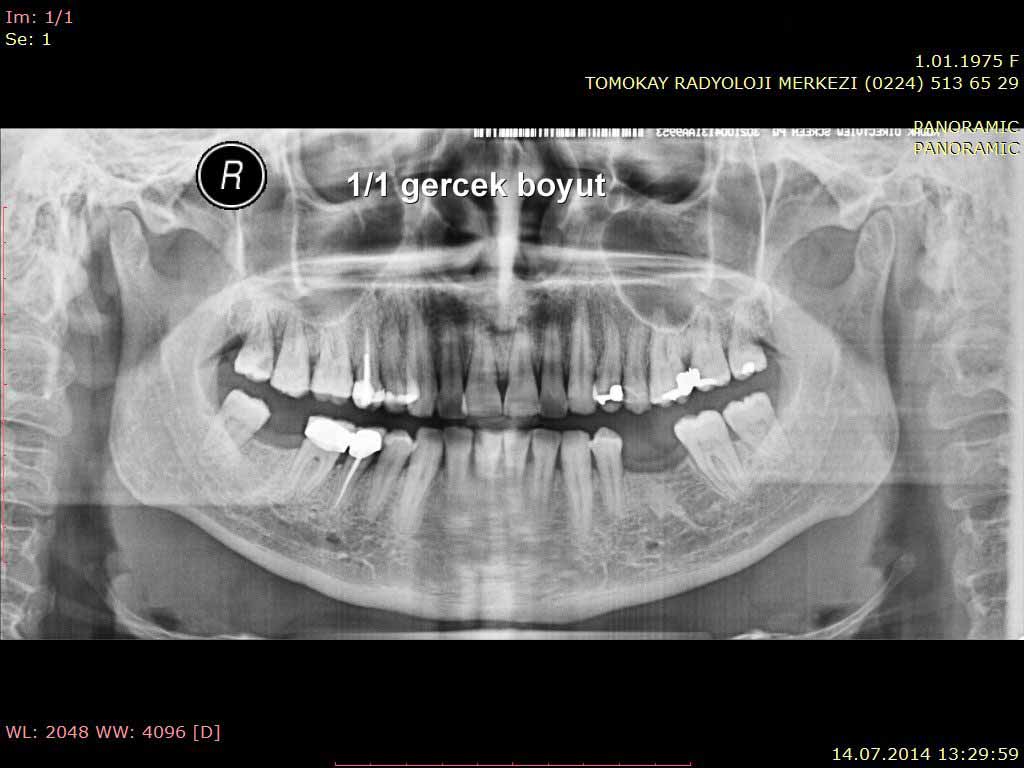

ما هو تصوير اشعة البانوراما للأسنان؟

يوفر إمكانية رؤية البنية التشريحية للأسنان والفكين في فيلم واحد على مستوى ثنائي الأبعاد.